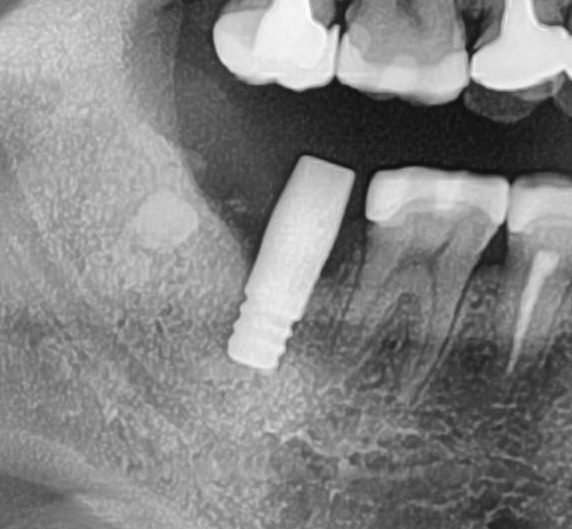

開けた穴に、専用道具を使ってネジを締めるように長さ2センチ程のインプラントを骨に埋め込んでいきます。

しっかりとインプラント埋め込まれた後は、動揺がないか、噛んだ時に当たらないかなどを確認して、最後にパノラマ写真を撮影して今回のオペは終了となりました。